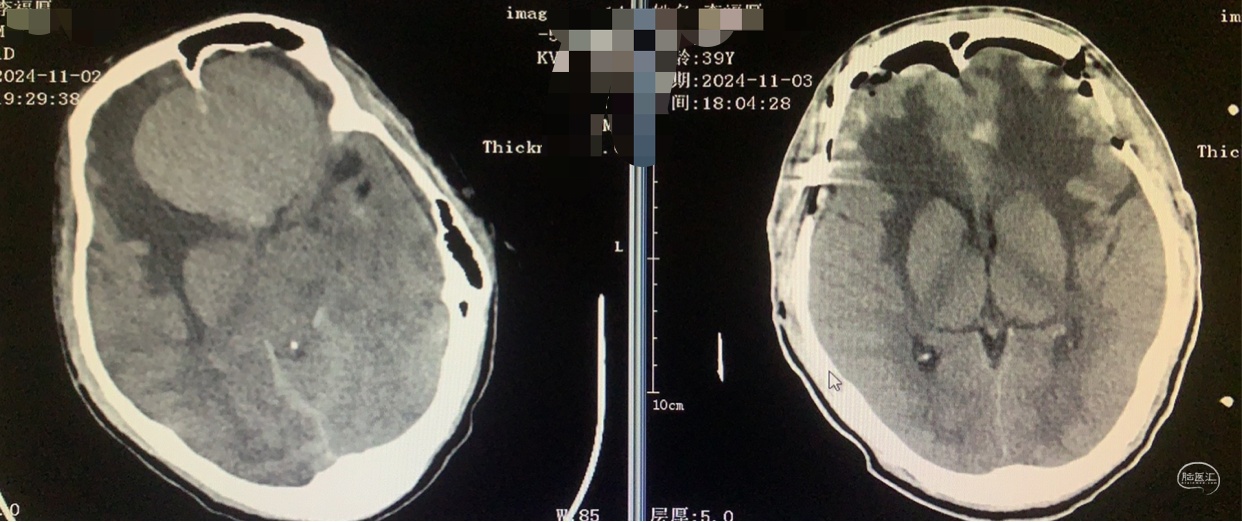

术前术后对比

术后24天步行出院。

2024.12.2步行返院复诊。

术后CT

术后16天患者步行出院。